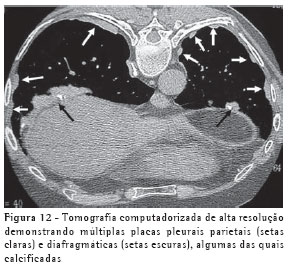

A TCAR é um método mais sensível e específico do que a radiografia. As placas pleurais são caracterizadas na TCAR como espessamentos pleurais focais, geralmente bilaterais, descontínuos, com bordas lisas, em platô, e por vezes com calcificações (Figura 12).(10-11)